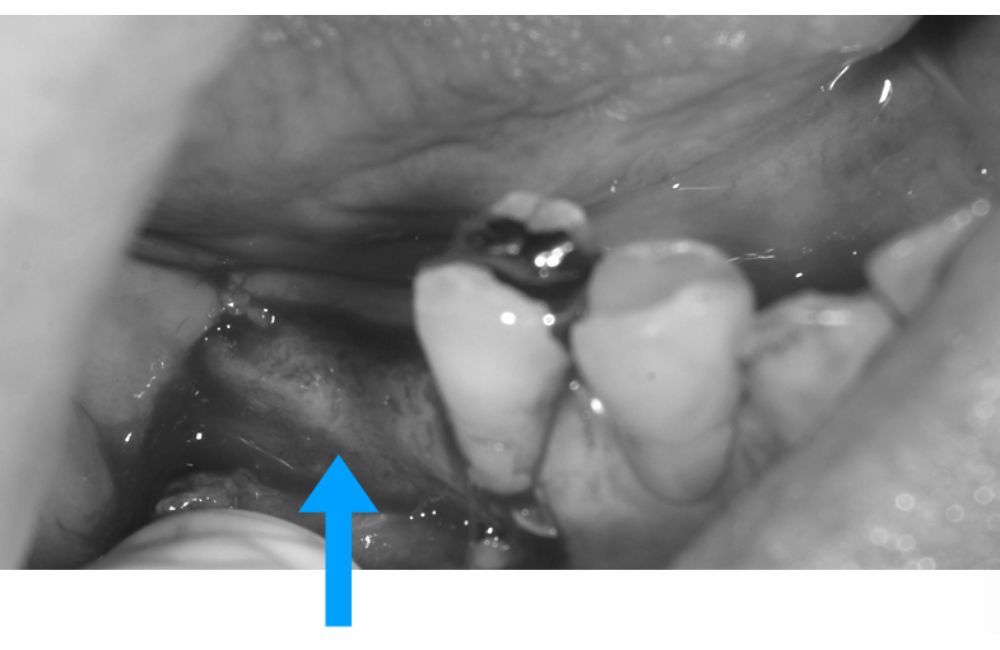

抜歯後に行ったソケットプリザベーション

骨と歯ぐきがある程度保存できたのでインプラントの難易度が下がりました。